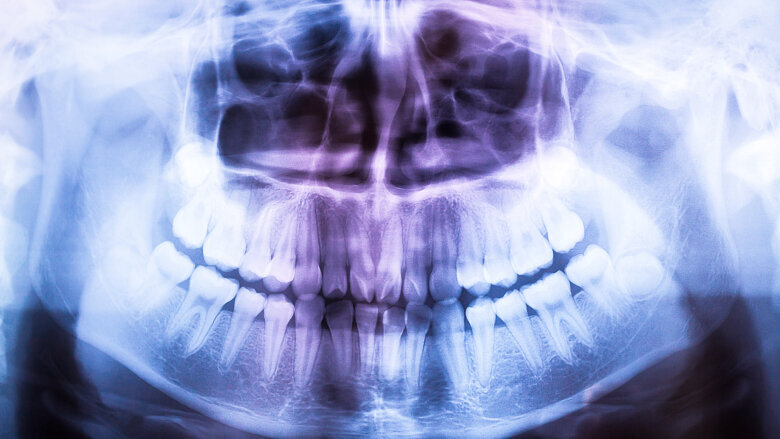

York (GB) ‒ Le radiografie sono utili in diagnostica, ma espongono i pazienti a radiazioni potenzialmente dannose. Quindi, ad ogni lastra che fanno, i dentisti sanno di dover calcolare accuratamente il rapporto costi/benefici per il paziente. Una ricerca condotta dall’Università di York ha scoperto che i dentisti sono più inclini a richiedere o effettuare radiografie se e quando vengono pagati per ogni lastra anche quando, tuttavia, non sia clinicamente necessaria.

Allorché i pazienti non pagavano, il numero delle radiografie era in crescita. Secondo uno studio pubblicato sull’ultimo Journal of Health Economics, comunque, se i dentisti erano a stipendio fisso venivano effettuate meno radiografie. L’analisi approfondita del Centre for Health Economics (Università di York) ha analizzato su un periodo di dieci anni, i dati sui dentisti operanti in Scozia: stipendiati o che ricevevano compensi per prestazioni a pagamento dal Servizio Sanitario Nazionale, NHS. La ricerca, in cui sono stati presi in considerazione oltre un milione di casi, ne ha confermato un’altra, più limitata avvenuta in precedenza, sui riflessi che diversi tipi di pagamento ai dentisti possono avere sull’intensità della cura e sulla frequenza dei controlli alla bocca.

«I nostri risultati mostrano che un certo modo di pagare il dentista si riflette significativamente sull’utilizzo dei raggi X, qualora i dentisti siano pagati con cifra a parte per ogni lastra che effettuano in più» dicono i ricercatori.

Pur auspicando un’indagine più approfondita, i ricercatori affermano che tali risultanze potrebbero avere un impatto significativo sulla politica della salute pubblica, in particolar modo, sulla protezione dei pazienti a sovraesposizione dai raggi X.

«Anche se dei pazienti dal punto di vista rischio-benefici potrebbero volontariamente decidere di ricevere un livello di raggi X apparentemente ottimale, sarebbe non di meno eticamente opinabile che la quantità di raggi X ricevuta dai pazienti esenti è significativamente più alta se chi somministra i raggi è pagato a prestazione o se percepisce uno stipendio» dicono.

«Ciò significa da un lato che il paziente trattato da dentisti stipendiati riceve meno raggi X di quelli ottimali per la sua salute orale, e dall’altro che quelli esenti se trattati da dentisti compensati a prestazione ne ricevono troppi»

Lo studio, intitolato “First do no harm—The impact of financial incentives on dental X-rays”, è stato pubblicato nell’edizione di Marzo 2018 del Journal of Health Economic.